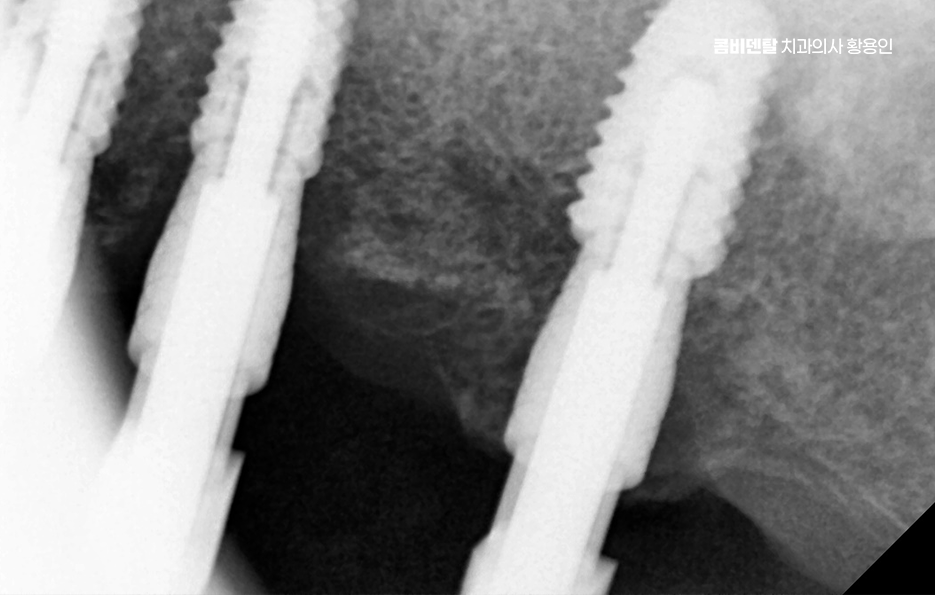

50대임플란트 치료는 시작 전에 정밀한 진단이 선행되어야 하는데 단순히 빈자리만 보고 이 자리에 임플란트를 하나씩 심는 방식이 아니라 턱뼈 상태, 잇몸 높이, 씹는 힘의 분포, 전체 교합의 불균형까지 전부 고려해야 안정적이고 오래 가는 치료가 될 수 있어요

그래서 CT 촬영으로 턱뼈의 두께, 밀도, 신경 위치를 정밀하게 확인하고 각 임플란트의 위치와 각도를 계획해야 하며 50대는 전신 건강 상태도 함께 고려해야 하는데 당뇨, 고혈압, 골다공증 같은 만성 질환이 있는 경우에는 임플란트 치료 시 잇몸 치유 속도나 골융합 반응이 다를 수 있기 때문에, 반드시 의료진과의 충분한 상담이 필요하고 약물 복용 여부나 치유 능력 등을 고려해 치료 시기와 방식을 1:1 맞춤형으로 계획하실 필요가 있어요